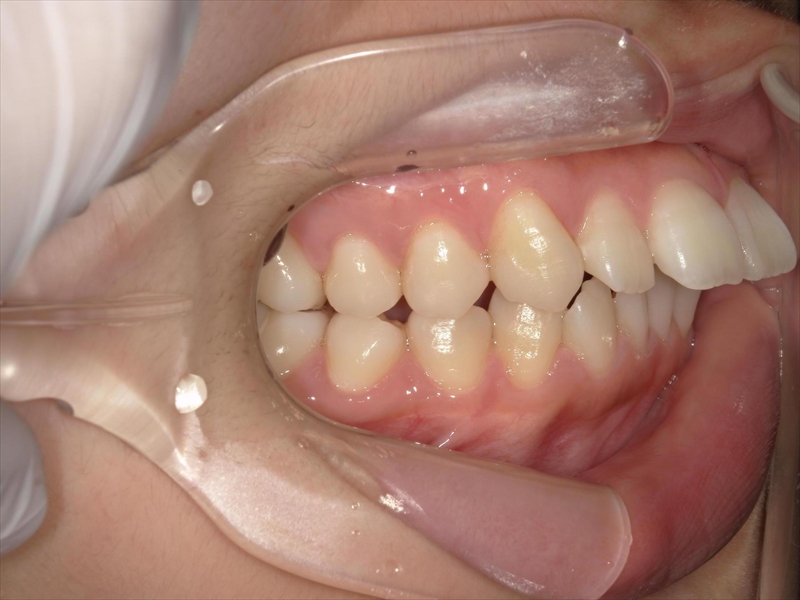

この患者様は、重度の出っ歯があり、下顎前歯には叢生が認められました。

また、奥歯の噛み合わせにも問題があり、本来は半歯分ずつずれて噛み合うべきところが、正しく機能していない状態でした。

その影響で咀嚼力は一般成人の約半分程度に低下しており、顎関節症の疑いもありました。

治療前後 写真